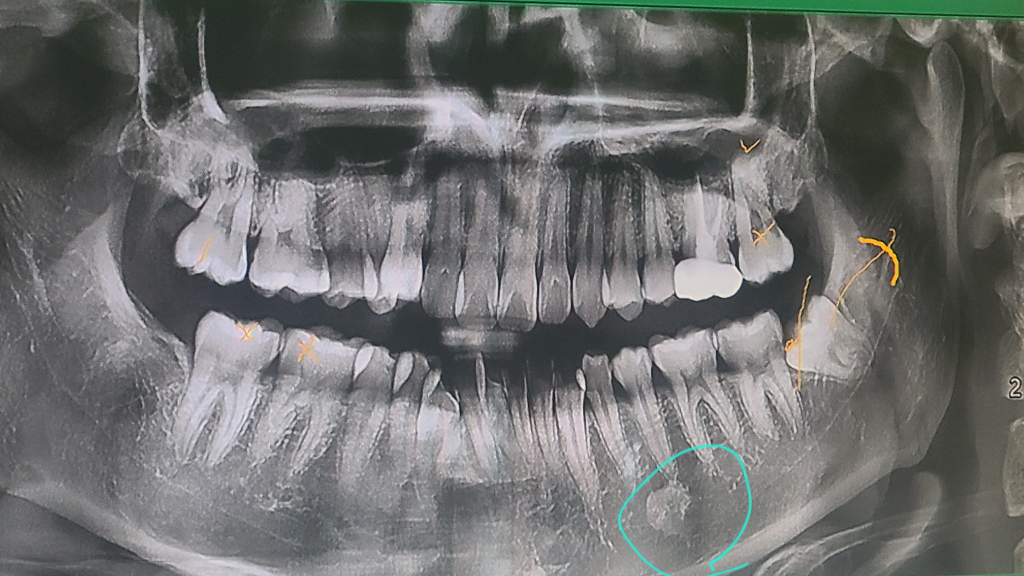

치과 CT에서 발견된 방사선불투과성 골내병소인데 저 죽나요?

오늘 사랑니 발치를 위해 CT촬영을 했는데 왼쪽 턱 밑에 0.8센치 정도의 방사선불투과설 골내병소가 관찰된다고 심각한 건 아닐 거니까 몇 달 뒤에 예방 차원으로 큰 병원 가보라고 의뢰서 써주셨는데 걱정 안 해도 될까요...? 너무 두렵네요

• 1번 째 사진

저 부위에 보이는 방사선불투과상은 크게 문제가 잇는게 아니고 환자분의 뼈가 경화된상태입니다. 크게 걱정하지 않으셔도 됩니다.

아마도 골종으로 의심됩니다. 골종이란 특정부위 골밀도가 높아져 x ray 상에서 희게 보이는 것으로 대부분 그냥 두면 됩니다.

대학병원 가서 진단받아보시면 되며 골경화증같으며 생명에 문제가 되지는 않고 치료를 하지도 않습니다.